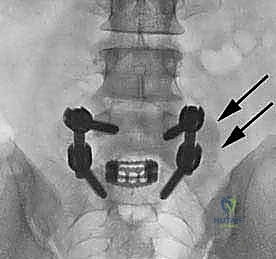

| عدد الأقفاص (Cages) | يتم وضع قفصين (واحد في كل جانب). | يتم وضع قفص واحد كبير مائل. |

الخطوة 4: زراعة القفص والطعم العظمي (Cage Insertion)

يتم إدخال قفص مصنوع من مادة PEEK أو التيتانيوم، مملوء بطعم عظمي (يؤخذ غالباً من المريض نفسه أو طعم صناعي)، في المساحة الفارغة. هذا القفص يعيد الارتفاع الطبيعي للفقرات ويخفف الضغط عن منافذ الأعصاب.